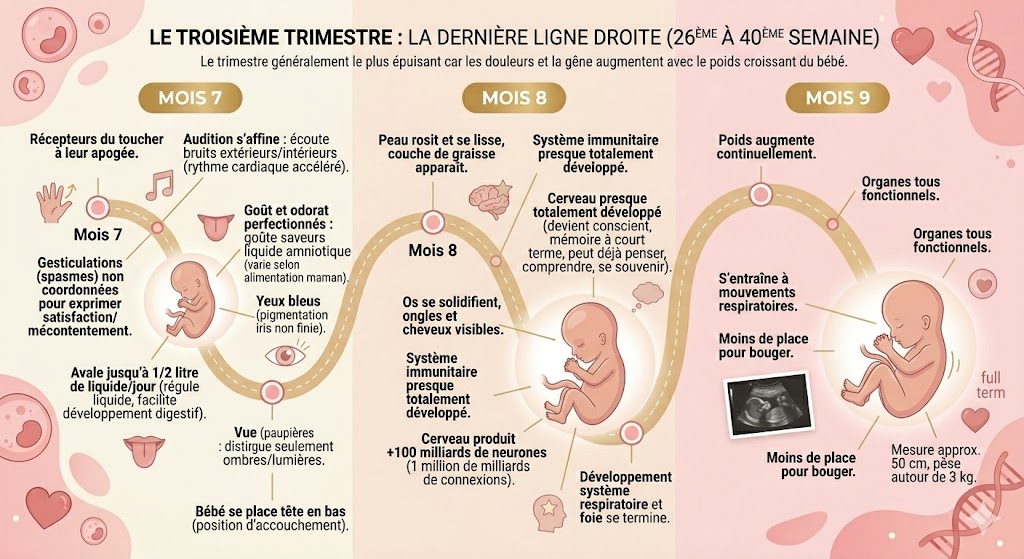

Développement du fœtus

Le troisième trimestre marque la dernière ligne droite. Il correspond généralement au trimestre le plus épuisant pour la future maman car les douleurs et la gêne augmentent en raison du poids croissant du bébé.

septième mois:

Lors du 7e mois de grossesse : le fœtus poursuit son développement dans le ventre de la maman. En effet, les récepteurs du toucher atteignent leur apogée lors de ce mois.

L’audition s’affine : le bébé peut écouter les bruits extérieurs et intérieurs qui font accélérer son rythme cardiaque. Il se met alors à bouger pour exprimer sa satisfaction ou son mécontentement, mais ses gesticulations ne sont pas coordonnées, ce sont plutôt des spasmes.

Par ailleurs, le fœtus perfectionne son goût et son odorat : il goûte aux saveurs du liquide amniotique qui varie en fonction de l’alimentation de la maman, il est capable d’avaler jusqu’à un demi litre de liquide amniotique chaque jour. Ceci lui permet notamment de réguler le niveau du liquide dans l’utérus et facilite le développement de son système digestif .

Cependant il ne peut pas encore travailler sa vue. Malgré que ses paupières puissent s’ouvrir vers la 24 ème semaine, il peut seulement distinguer des alternances d’ombres et de lumières. De plus, la plupart des fœtus ont les yeux bleus car la pigmentation de l’iris n’est pas finie. Au cours de ce mois, le bébé se place en position d’accouchement avec la tête en bas.

Huitième mois:

Au 8e mois : le fœtus finit de prendre forme et termine les petits détails de son apparence :

La peau du fœtus rosit et se lisse, une couche de graisse apparaît. Les os du bébé se solidifient et les ongles et les cheveux sont visibles. De plus le système immunitaire et le cerveau du bébé sont presque totalement développés. En effet, il devient conscient et crée même une mémoire à court terme et peut déjà penser comprendre et se souvenir. Le cerveau produit plus de 100 milliards de neurones qui assurent déjà un million de milliards de connexions. Enfin, le mois se termine par le développement du système respiratoire et du foie.

Neuvième mois:

Au 9e mois : le fœtus continue de prendre du poids, ses organes sont tous fonctionnels et il s’entraîne déjà à réaliser des mouvements respiratoires ! Cependant, il a de moins en moins de place pour bouger : à ce stade, le futur bébé mesure 50 cm et pèse autour de 3 kg.